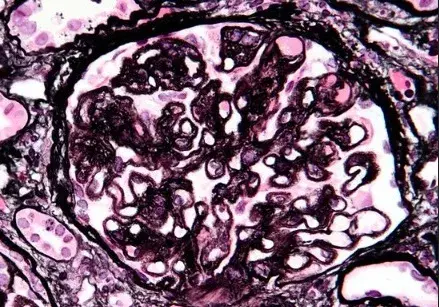

Nefropatía Membranosa: ¿Y si el paciente no responde al tratamiento inicial?

Nefropatía Membranosa: ¿Y si el paciente no responde al tratamiento inicial?

Cómo tratar la Nefropatía Membranosa de manera práctica

Cómo tratar la Nefropatía Membranosa de manera práctica